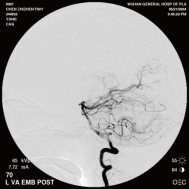

右侧颈内动脉后交通动脉瘤栓塞术前 左椎动脉造影 示左椎动脉夹层动脉瘤: 左椎动脉发出小脑后下动脉处呈囊性扩张,动脉瘤远端血管狭窄

颈内动脉创伤性假性动脉瘤覆膜支架治疗前后(三维像是术前) 右侧颈内动脉后交通动脉瘤栓塞术后完全闭塞

弹簧圈栓塞后造影示左椎动脉夹层动脉瘤消失, 左椎动脉、 多发动脉瘤夹闭术前、术中

左侧小脑后下动脉循环通畅